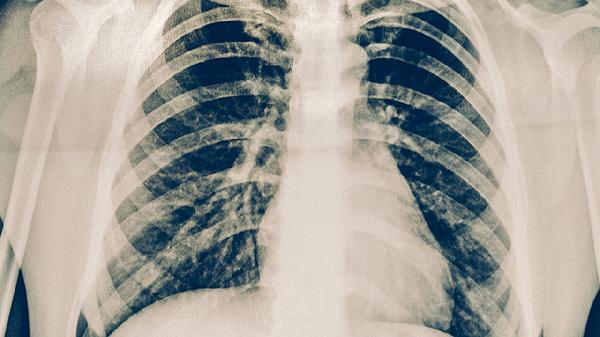

活動性肺結(jié)核可通過規(guī)范用藥、營養(yǎng)支持、隔離防護(hù)、定期復(fù)查、心理疏導(dǎo)等方式治療。活動性肺結(jié)核通常由結(jié)核分枝桿菌感染引起,主要表現(xiàn)為咳嗽、咯血、低熱、盜汗等癥狀。

治療期間每月需復(fù)查痰涂片、胸部X線及肝腎功能。痰菌轉(zhuǎn)陰后仍需完成全程治療。治愈后每3-6個月隨訪1次,持續(xù)2年觀察復(fù)發(fā)跡象。若出現(xiàn)體重驟降、咳嗽加重等癥狀需立即復(fù)診。